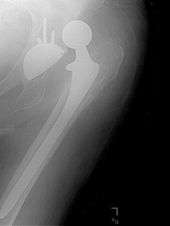

Femoral component

The femoral component is the component that fits in the femur (thigh bone). Bone is removed and the femur is shaped to accept the femoral stem with attached prosthetic femoral head (ball). There are two types of fixation: cemented and uncemented. Cemented stems use acrylic bone cement to form a mantle between the stem and to the bone. Uncemented stems use friction, shape and surface coatings to stimulate bone to remodel and bond to the implant. Stems are made of multiple materials (titanium, cobalt chromium, stainless steel, and polymer composites) and they can be monolithic or modular. Modular components consist of different head dimensions and/or modular neck orientations; these attach via a taper similar to a Morse taper. These options allow for variability in leg length, offset and version. Femoral heads are made of metal or ceramic material. Metal heads, made of cobalt chromium for hardness, are machined to size and then polished to reduce wear of the socket liner. Ceramic heads are more smooth than polished metal heads, have a lower coefficient of friction than a cobalt chrome head, and in theory will wear down the socket liner more slowly. As of early 2011, follow-up studies in patients have not demonstrated significant reductions in wear rates between the various types of femoral heads on the market. Ceramic implants are more brittle and may break after being implanted.